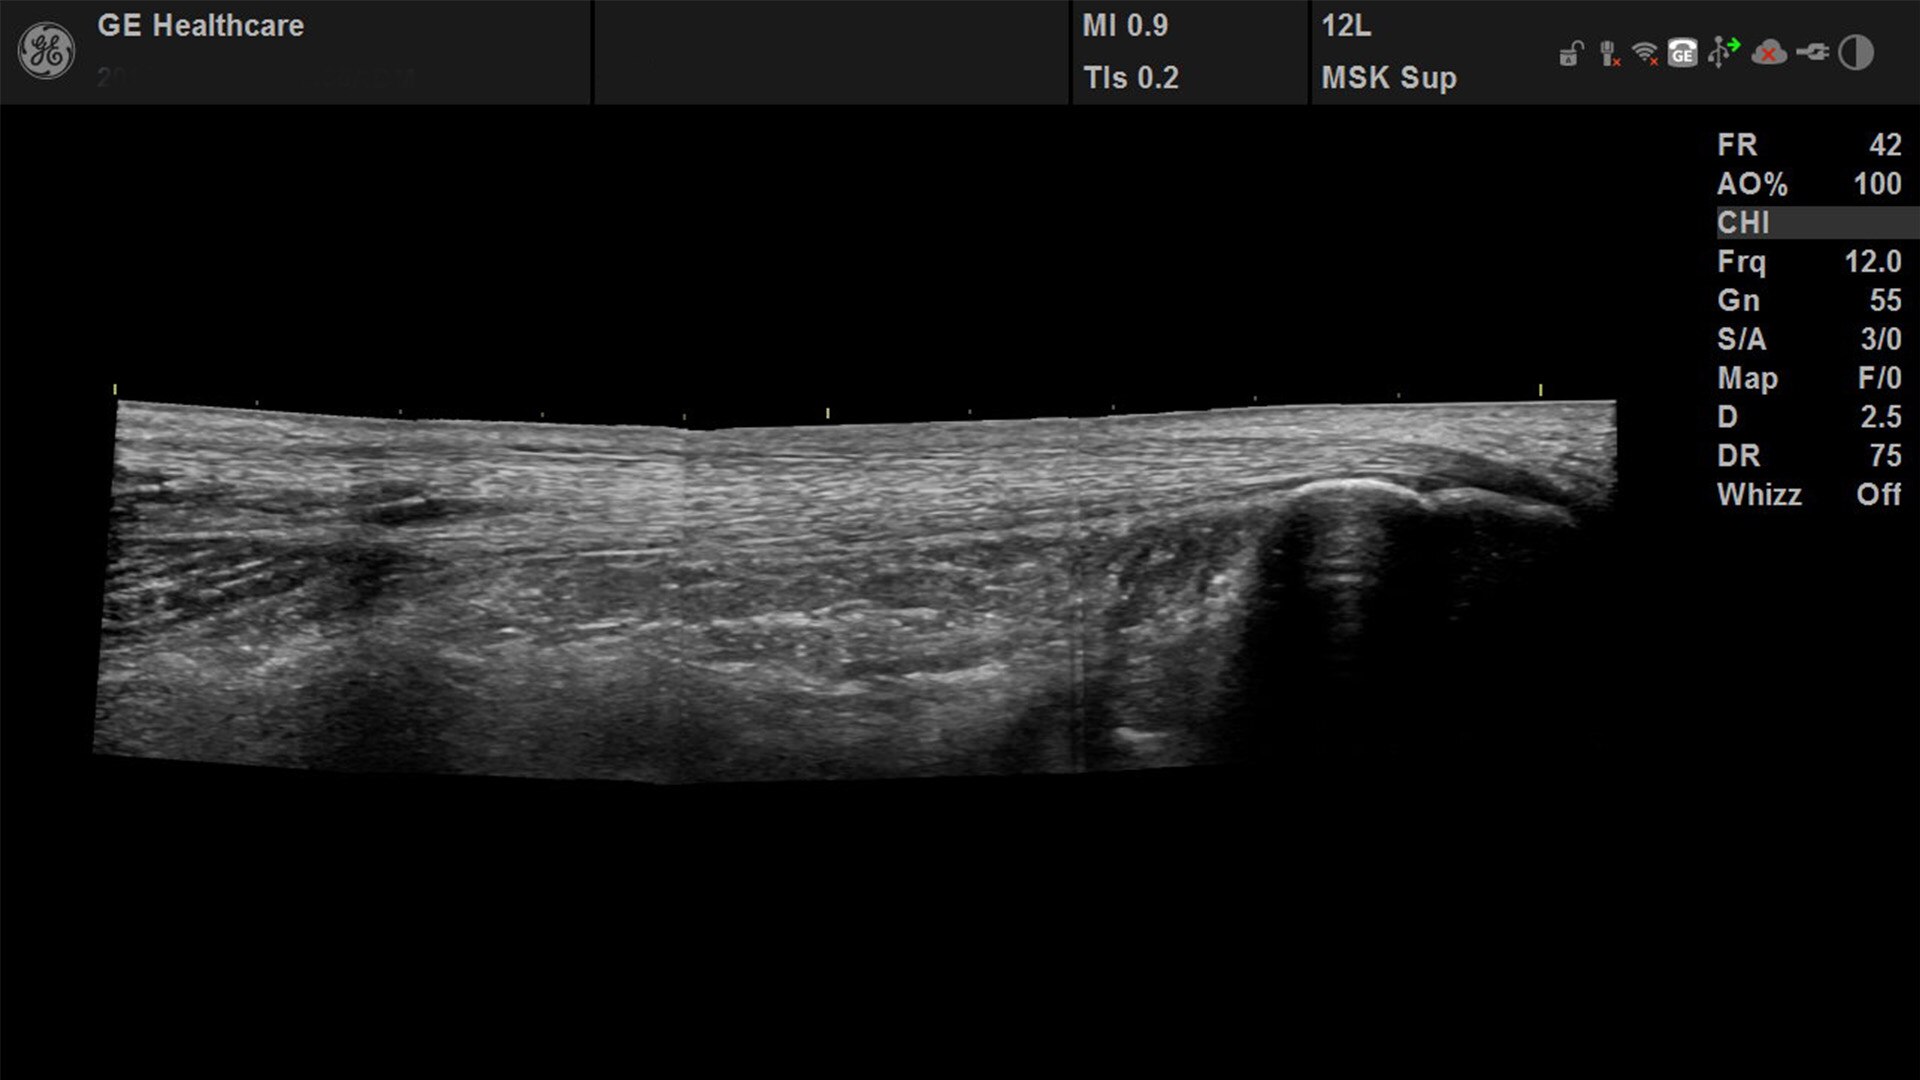

Suited for abdominal, small parts, cardiac, OB/GYN, vascular, and MSK exams

Versana Active delivers the imaging capability of a console in a hand-carried, lightweight package that enables you to actively take your system to your patients, on premises, or remote facilities. The reliable system brings the agility of a laptop unit with the capability for attaching to a cart. Adaptable to cover a broad range of everyday exams, it is easy to carry to clinics, offices, and beyond.

Versana Active features a wide range of advanced clinical applications and automated tools that simplify exams, streamline workflow, and enable fast, high-volume scanning to help you diagnose a wide spectrum of patient conditions.